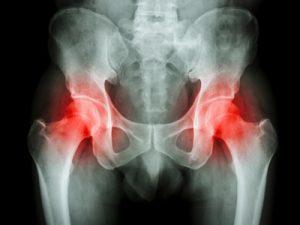

股関節の症状

変形性股関節症

| 症状 | 変形の初期には脚の付け根や臀部(でんぶ)、膝の上部のこわばりや重い感じがあり、歩き始めや長時間の歩行、階段の昇降で痛みが起こります。腰からのいわゆる坐骨神経痛(ざこつしんけいつう)や変形性膝関節症に症状が似ている場合があります。初期でも炎症が強く関節液がたまっていたり、関節唇(しん)が損傷されていたりする場合には比較的に強い痛みがあります。 変形が進行し進行期から末期になるにつれ、動きが制限されて痛みも強くなり、筋力も低下してきます。長距離の歩行や階段の昇降、しゃがみ立ちが困難になるなど徐々に日常生活が制限されてきます。 |

| 治療 | 保存的治療として痛みに対して体重のコントロールや安静、杖の使用、温熱療法などの理学療法、湿布、塗り薬、痛み止めの内服薬などを用います。また股関節周囲の筋力トレーニングも有効です。股関節の重度の変形があり、日常生活に支障がある場合には、人工股関節手術が行われます。 |